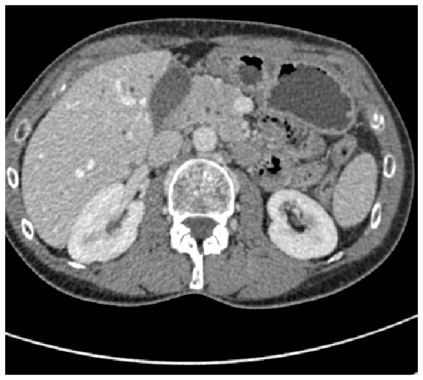

Medical image segmentation remains particularly challenging for complex and low-contrast anatomical structures. In this paper, we introduce the U-Transformer network, which combines a U-shaped architecture for image segmentation with self- and cross-attention from Transformers. U-Transformer overcomes the inability of U-Nets to model long-range contextual interactions and spatial dependencies, which are arguably crucial for accurate segmentation in challenging contexts. To this end, attention mechanisms are incorporated at two main levels: a self-attention module leverages global interactions between encoder features, while cross-attention in the skip connections allows a fine spatial recovery in the U-Net decoder by filtering out non-semantic features. Experiments on two abdominal CT-image datasets show the large performance gain brought out by U-Transformer compared to U-Net and local Attention U-Nets. We also highlight the importance of using both self- and cross-attention, and the nice interpretability features brought out by U-Transformer.